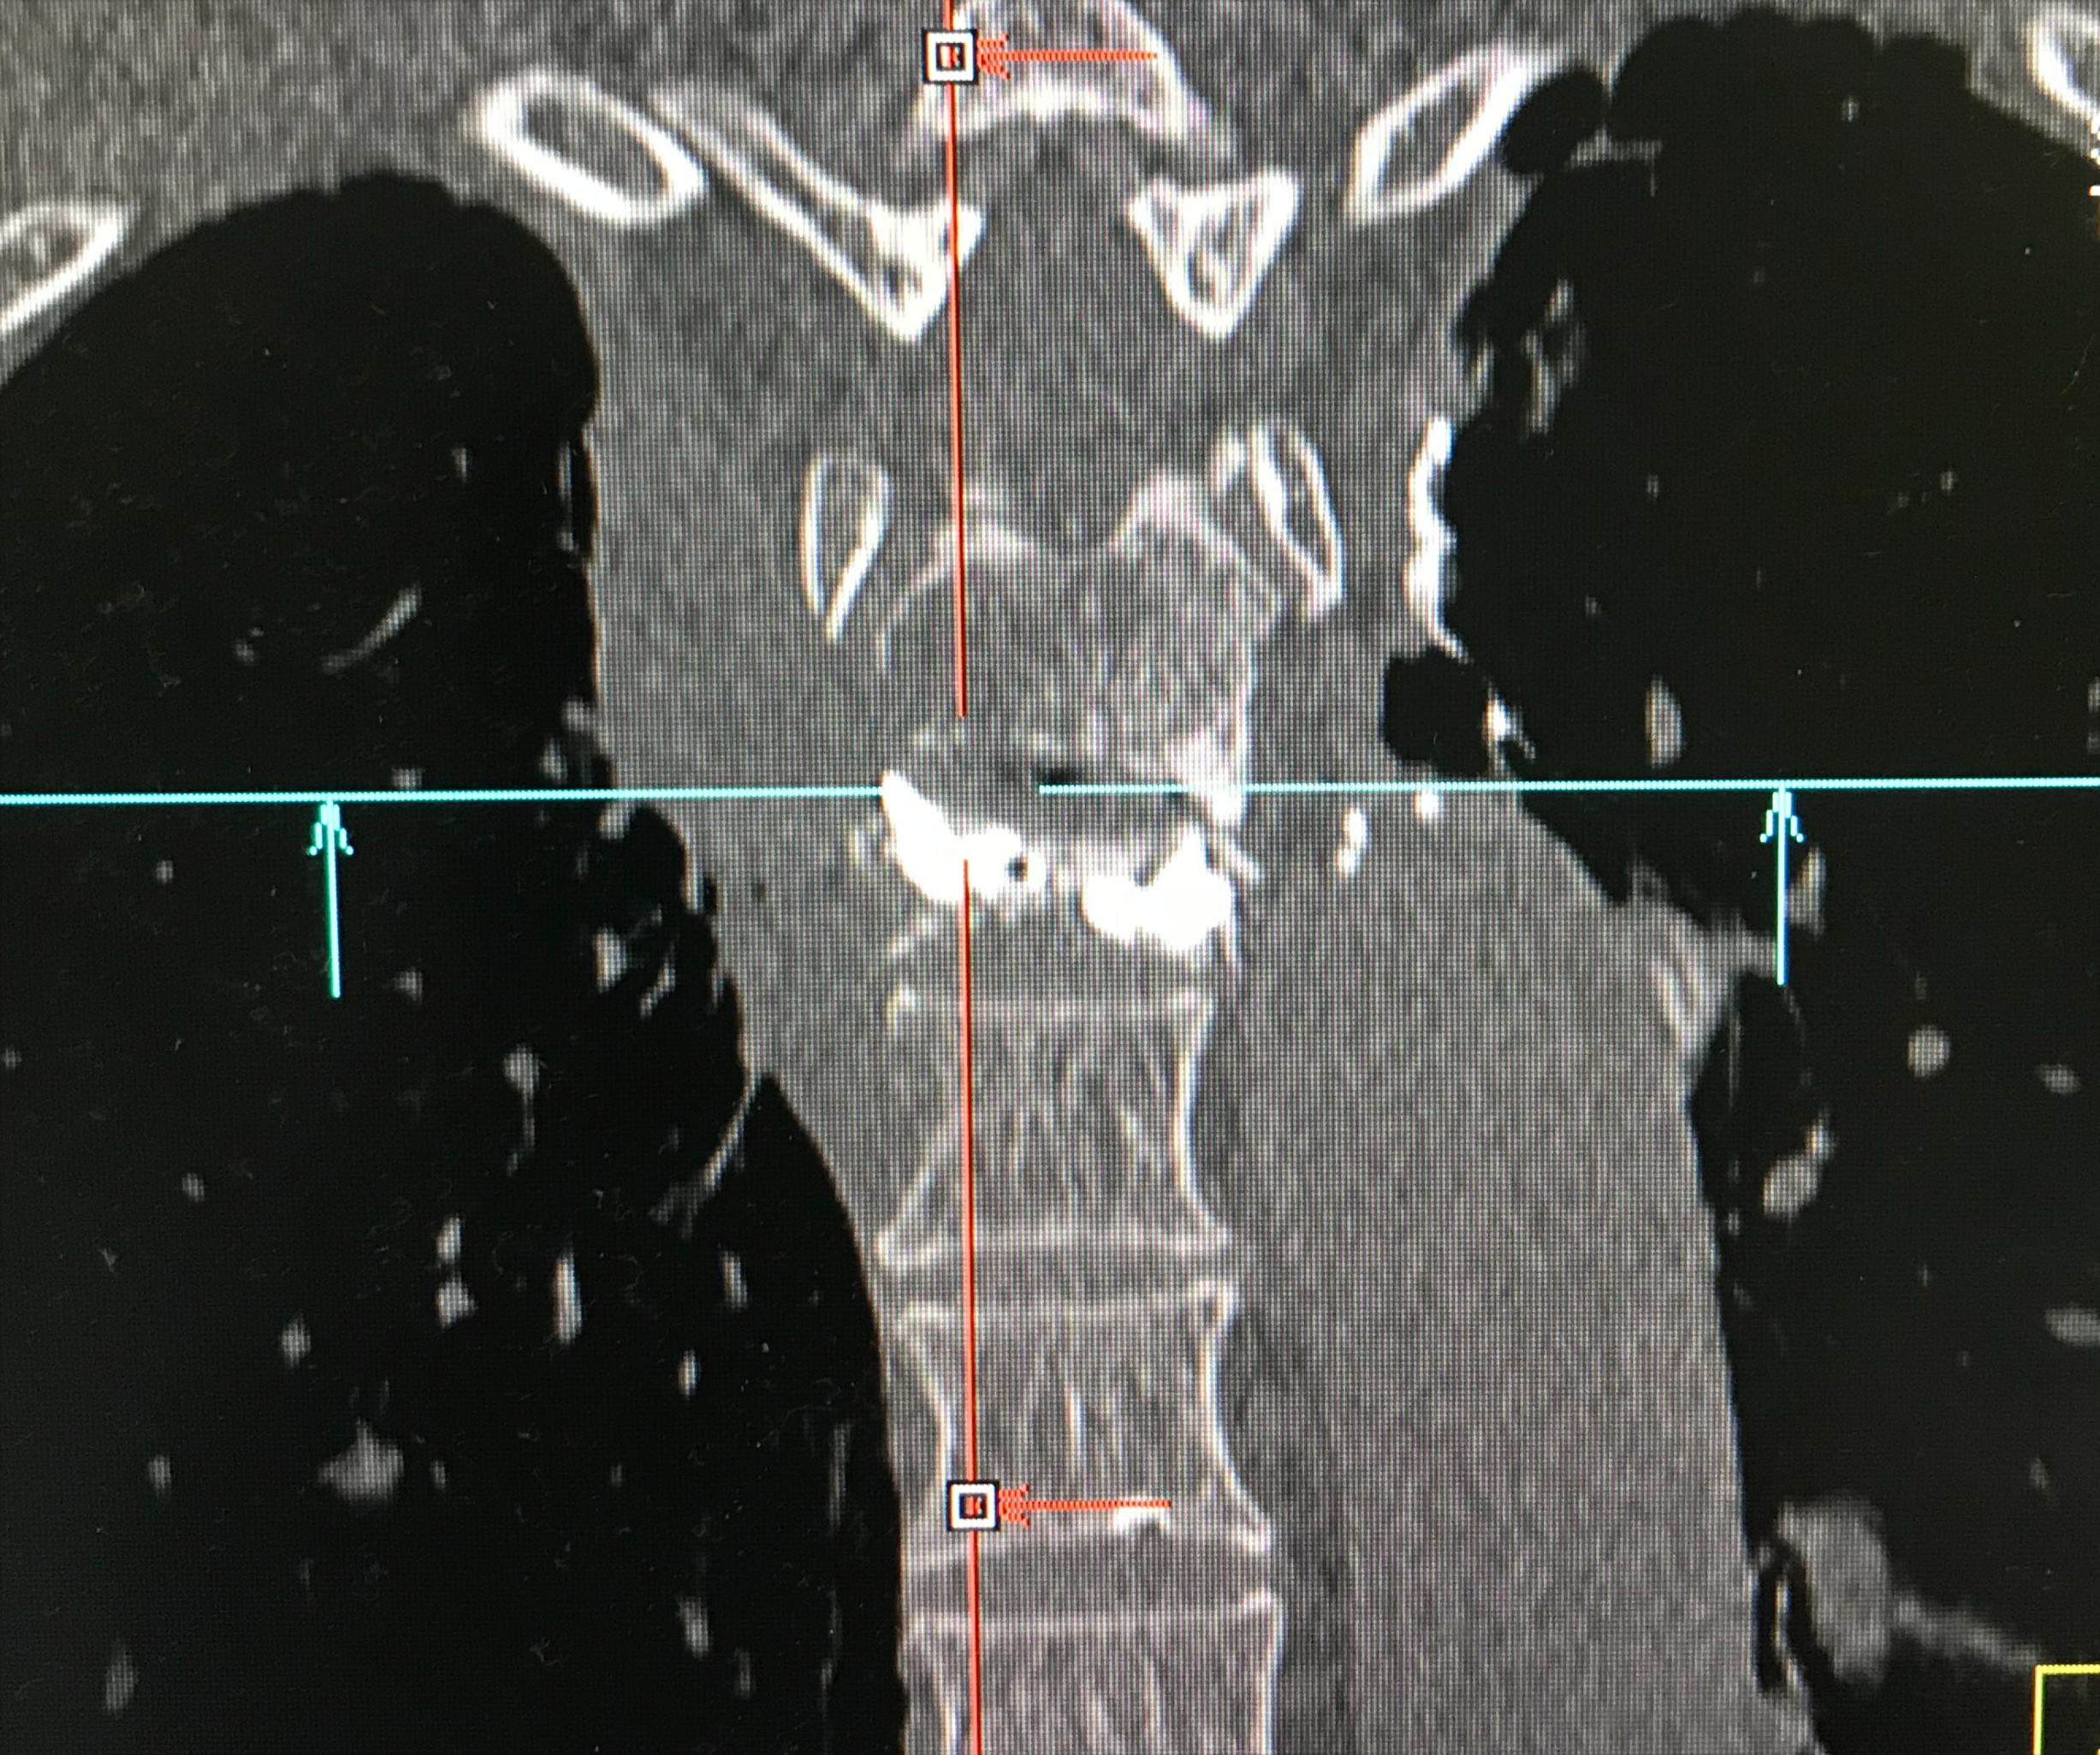

经皮椎体成形术术后进行CT扫描,重建后显示骨水泥在T5椎体内充填到位,且分布良好。

PVP术后冠状位重建示骨水泥分布良好